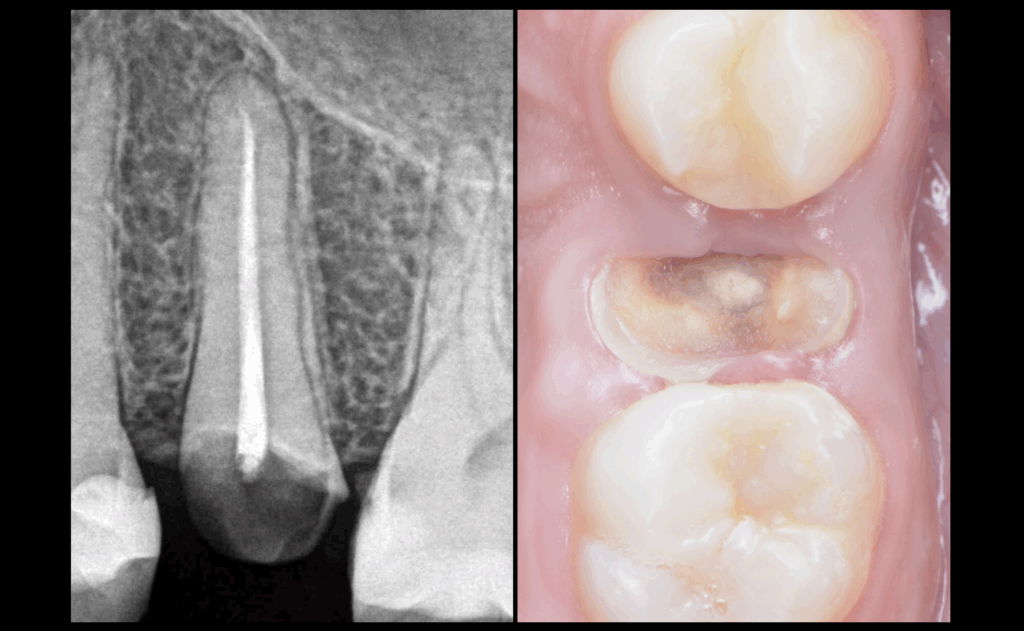

📉 Étant donné les 𝐦𝐚𝐮𝐯𝐚𝐢𝐬 𝐩𝐫𝐨𝐧𝐨𝐬𝐭𝐢𝐜𝐬 𝐛𝐢𝐨𝐦𝐞́𝐜𝐚𝐧𝐢𝐪𝐮𝐞𝐬 𝐞𝐭 𝐩𝐫𝐨𝐭𝐡𝐞́𝐭𝐢𝐪𝐮𝐞𝐬 de cette 25, considérons qu’elle soit à extraire.